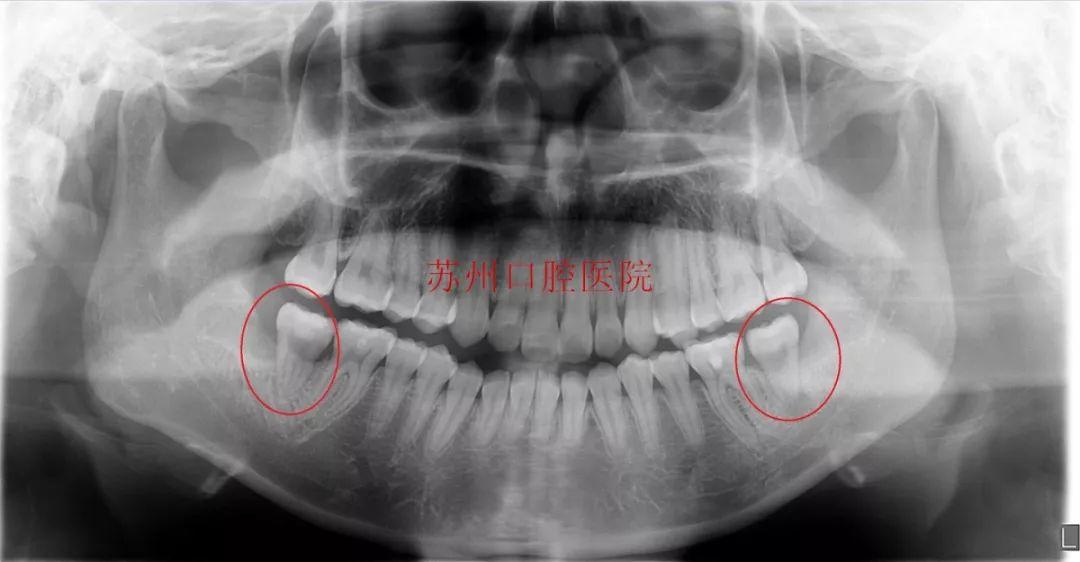

以醫(yī)院曾經(jīng)接到的患者病例舉例:有一位年輕的小姐姐,因飽受智齒發(fā)炎和磨牙齲壞的雙重疼痛,來院檢查后,常規(guī)方案需要拔除4顆牙再種植2顆牙,在經(jīng)濟(jì)和創(chuàng)傷方面都耗費(fèi)較大。

(移植前)

醫(yī)院牙體牙體牙髓科主任給患者做了檢查后,確定患者口內(nèi)情況:

常規(guī)方案是患者左右下頜都有兩顆橫位阻生的智齒,沒有及時(shí)拔除,現(xiàn)在這兩顆智齒引起前面7號(hào)牙的嚴(yán)重齲壞,按常規(guī)調(diào)節(jié)方案需要拔除兩顆智齒,以及智齒前方的兩顆7號(hào)牙,一共要拔除四顆牙齒,然后再種植兩顆牙。